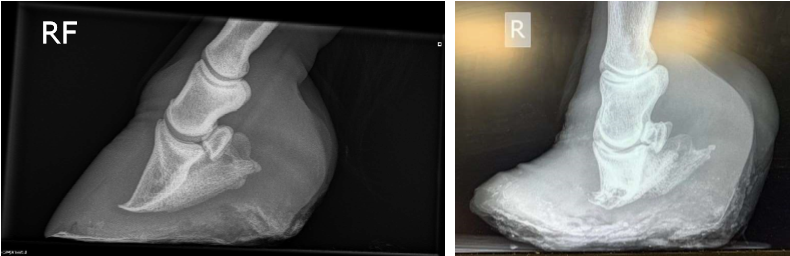

• what can be seen in this image?

collapse on the medial side

• On radiography, rotation / dropping of P3, remodelling / degeneration at the tip of P3 may be seen and rarely collapse on just the lateral or medial side